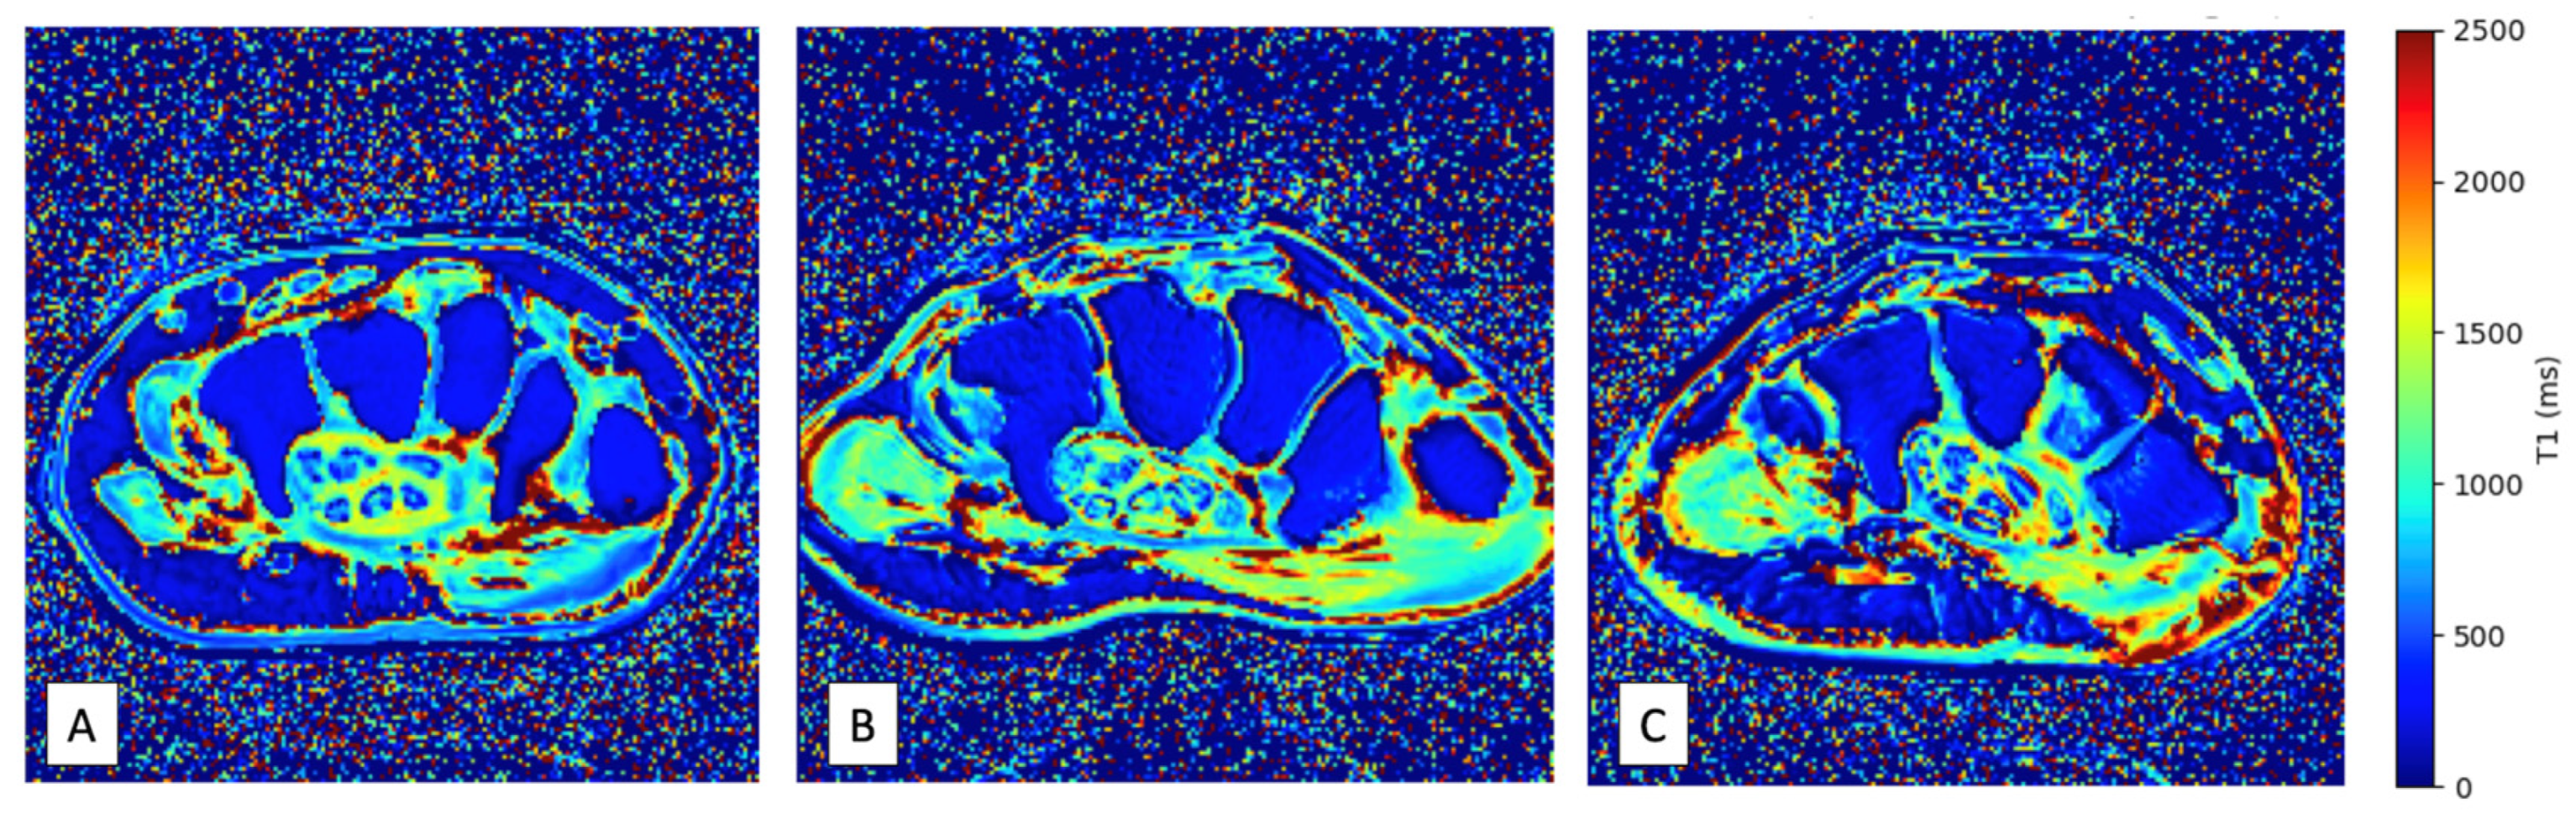

2.3. Image Acquisition

Figure 2. Examples of T1 mapping wrist images obtained in ATTR-CA patients with (A) and without (B) CTS, and in a healthy volunteer (C).